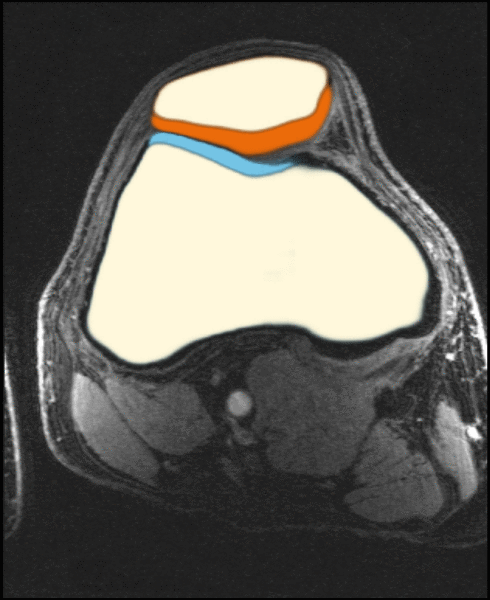

- analysis of cartilage thickness for ostheoarthitis assessment

- High-resolution data is from the University of Freiburg (T. Lange, K. Izadpanah)

- patellofemoral joint (prospective motion correction)

- depicted image is a healthy volunteer